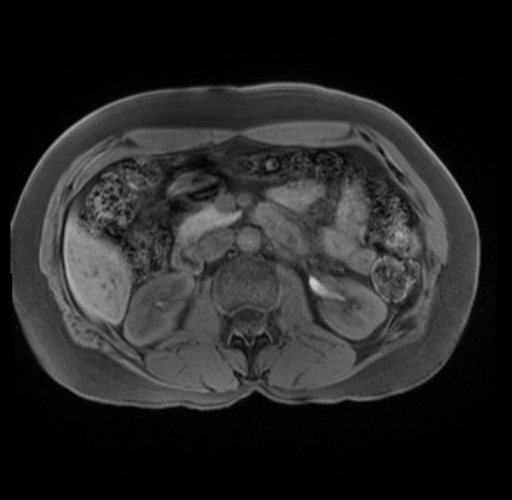

Imaging Analysis

Look through the patient's CT scan to identify any areas of concern for the necessary procedure.

Based on your CT findings, which issue(s) are present and would give reason for "planned slowing down moment(s)" in this case?